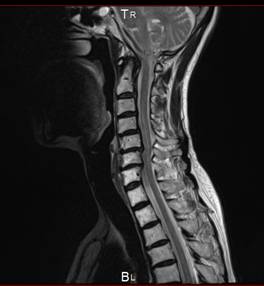

MRI 画像

頚椎、腰椎、のヘルニア、狭窄で痛み、痺れ、マヒ、不眠、が診られ

治療後は症状がとれて痛みや不眠から解放されました。

結果手術をしなくて良くなりました。